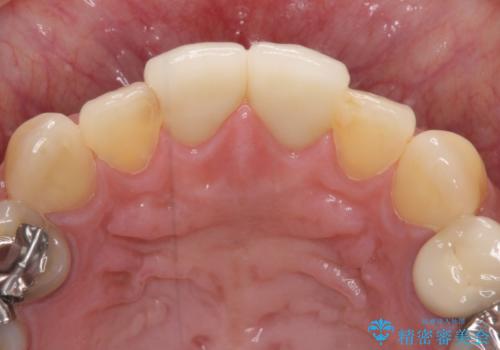

- 何度もコンポジットレジンによる修復を繰り返した結果、冷たいものがしみるようになってしまったとのことで来院された患者様です。

前歯2本が捻れている形態も気になるとのことであったので、虫歯の治療を兼ねて、オールセラミッククラウンにて補綴治療を行うこととしました。

2本とも治療前の歯髄の状態は正常でしたが、補綴治療により歯を大きく削ることになるため、歯髄が炎症を起こすリスクがあることを了解いただきました。

色彩や形態が大きく改善されたことはもちろん、虫歯によってしみていた症状もなくなり、患者様には大変満足していただきました。